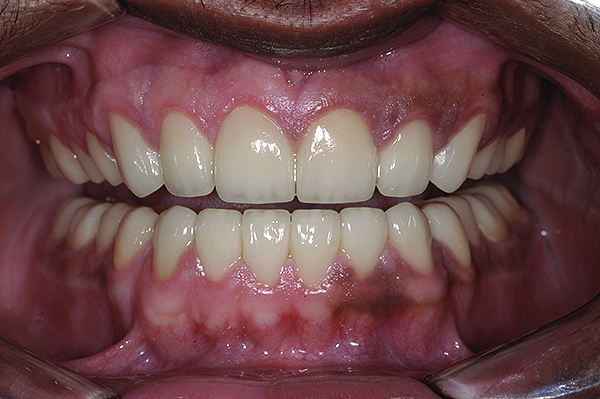

Figure 23. Postoperative 1:1 retracted frontal view.

Figure 23

The final restorations depicted restoration of form, function, and beauty, with good harmony of restoration and the periodontium (Figure 19 through Figure 25). MIP was in harmony with CR, and right and left lateral excursion discluded all posteriors with anterior group function. The postoperative orthopantomogram (OPG) (Figure 26) shows the treatment done while maintaining the vitality of anterior teeth.